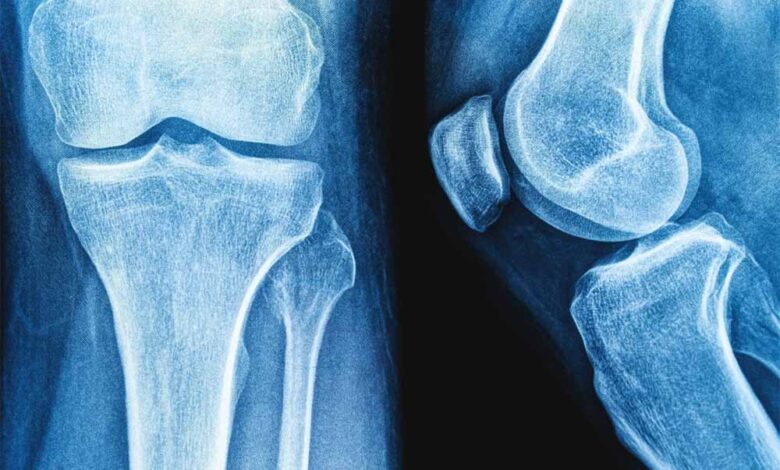

हड्डियों की मरम्मत के लिए प्रोटीन से नए उपचार के रास्ते – Khabar Jagat

राउरकेलाराष्ट्रीय प्रौद्योगिकी संस्थान (एनआईटी) राउरकेला के शोधकर्ताओं ने मानव शरीर में पाई जाने वाली प्राकृतिक शर्करा जैसे अणु हड्डियों के निर्माण और मरम्मत के लिए जिम्मेदार प्रोटीन, बोन मॉर्फोजेनेटिक प्रोटीन-2…